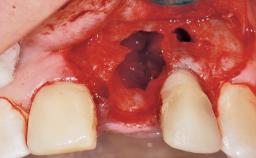

Immediate Flapless Placement of an Implant in a Maxillary Right Lateral Incisor Site

This 43-year-old male patient, a non-smoker, came to our practice because of a fracture of tooth 12 caused by a bicycle accident. Due to the combined para- and infrabony crown and root fracture, tooth extraction, and subsequent implant placement were suggested to the patient as the therapy of choice. The patient had high esthetic expectations with regard to the treatment outcome and asked for an immediate fixed provisional restoration. His individual esthetic risk profile summed up to a medium esthetic risk.

Placement Protocol Immediate implant placement

Socket Morphology Single-root socket

Socket Integrity Sufficient, with intact bone walls